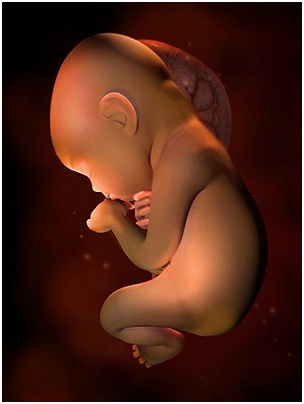

怀孕第28周胎儿图 从现在开始,你就进入了孕晚期,要注意的事情很多呦!你要每天做胎动...

怀孕第28周胎儿图 从现在开始,你就进入了孕晚期,要注意的事情很多呦!你要每天做胎动... -